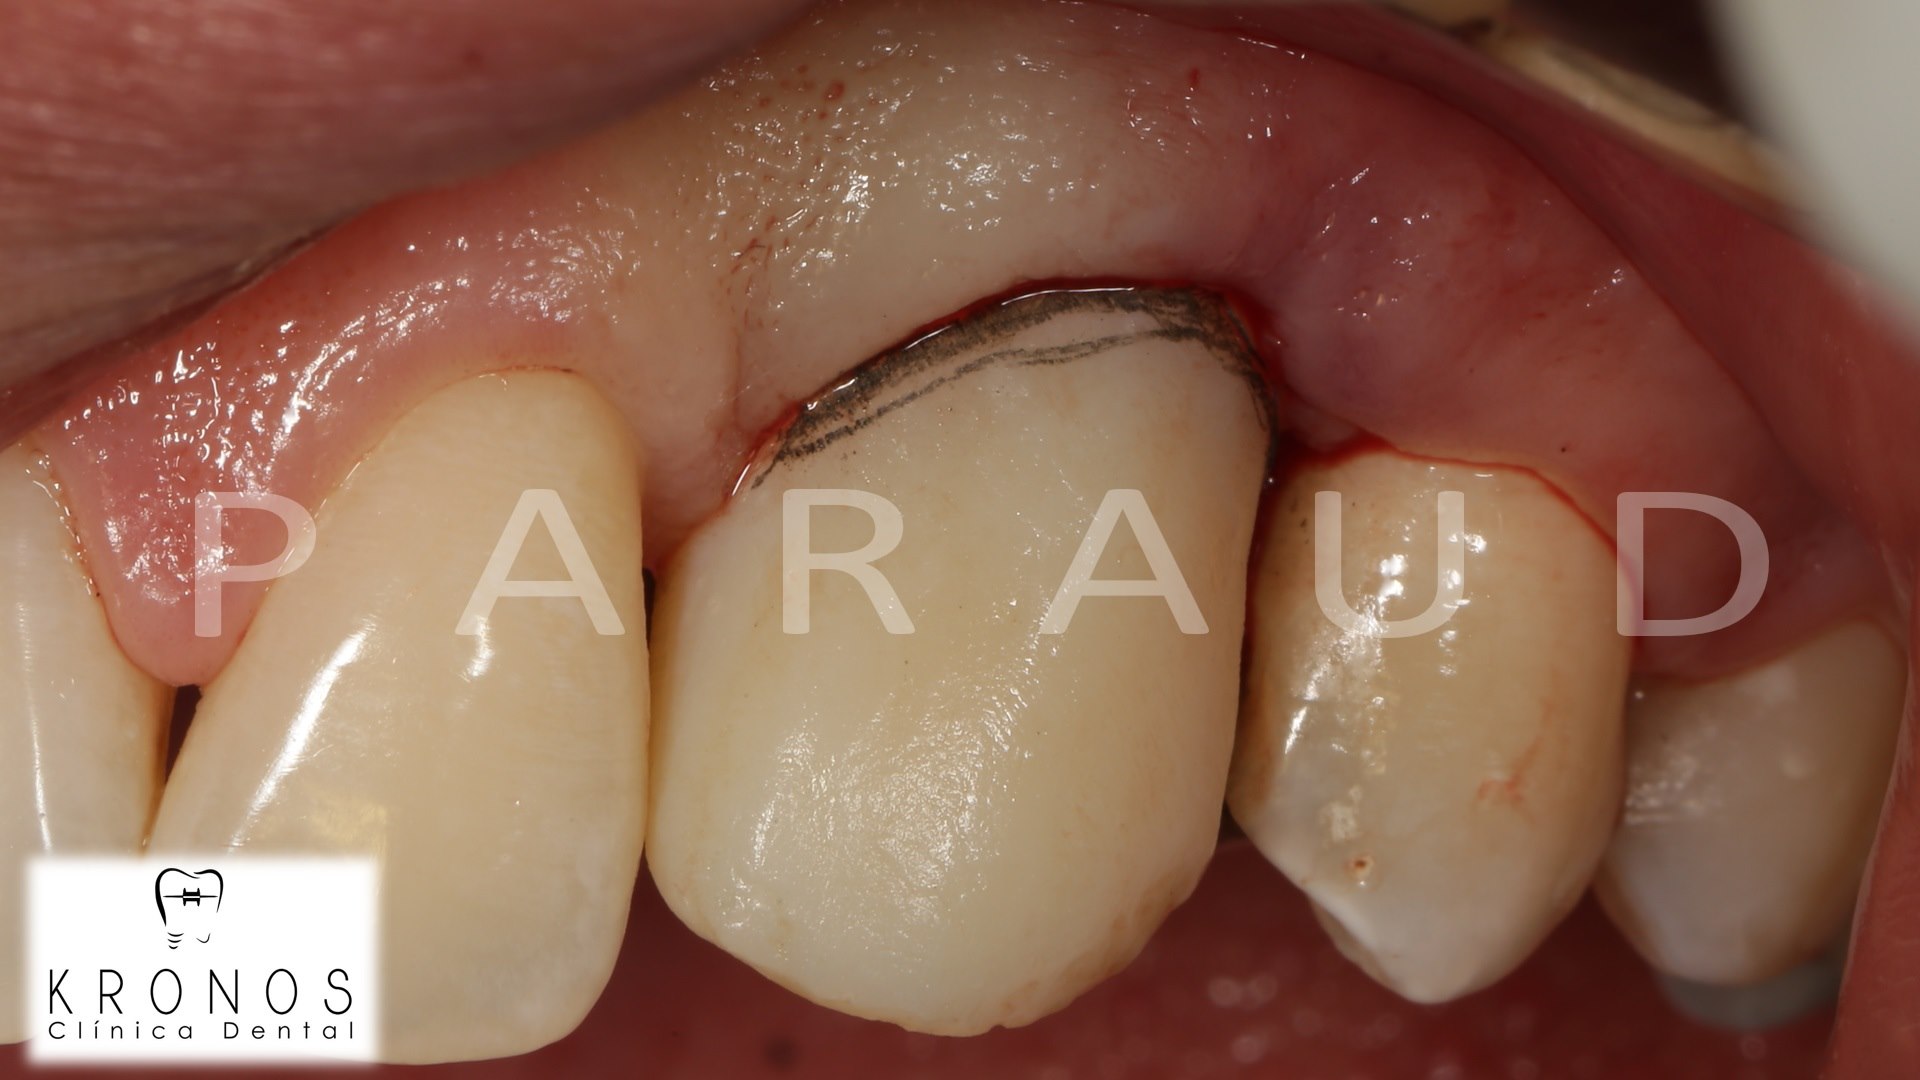

Clinical case: AnyRidge immediate loading

- Courtesy of Dr. Andres Paraud Freixas, Chile -

AnyRidge, ISQ value, initial stability, immediate loading, KnifeThread, maxillary anterior, Mega ISQ, Dr. Andres Paraud Freixas

AnyRidge implant system, Mega ISQ, Digital prosthesis

“Patient’s smile was recovered on the day of surgery

with reliable & highly-aesthetic results using AnyRidge & R2GATE. ”